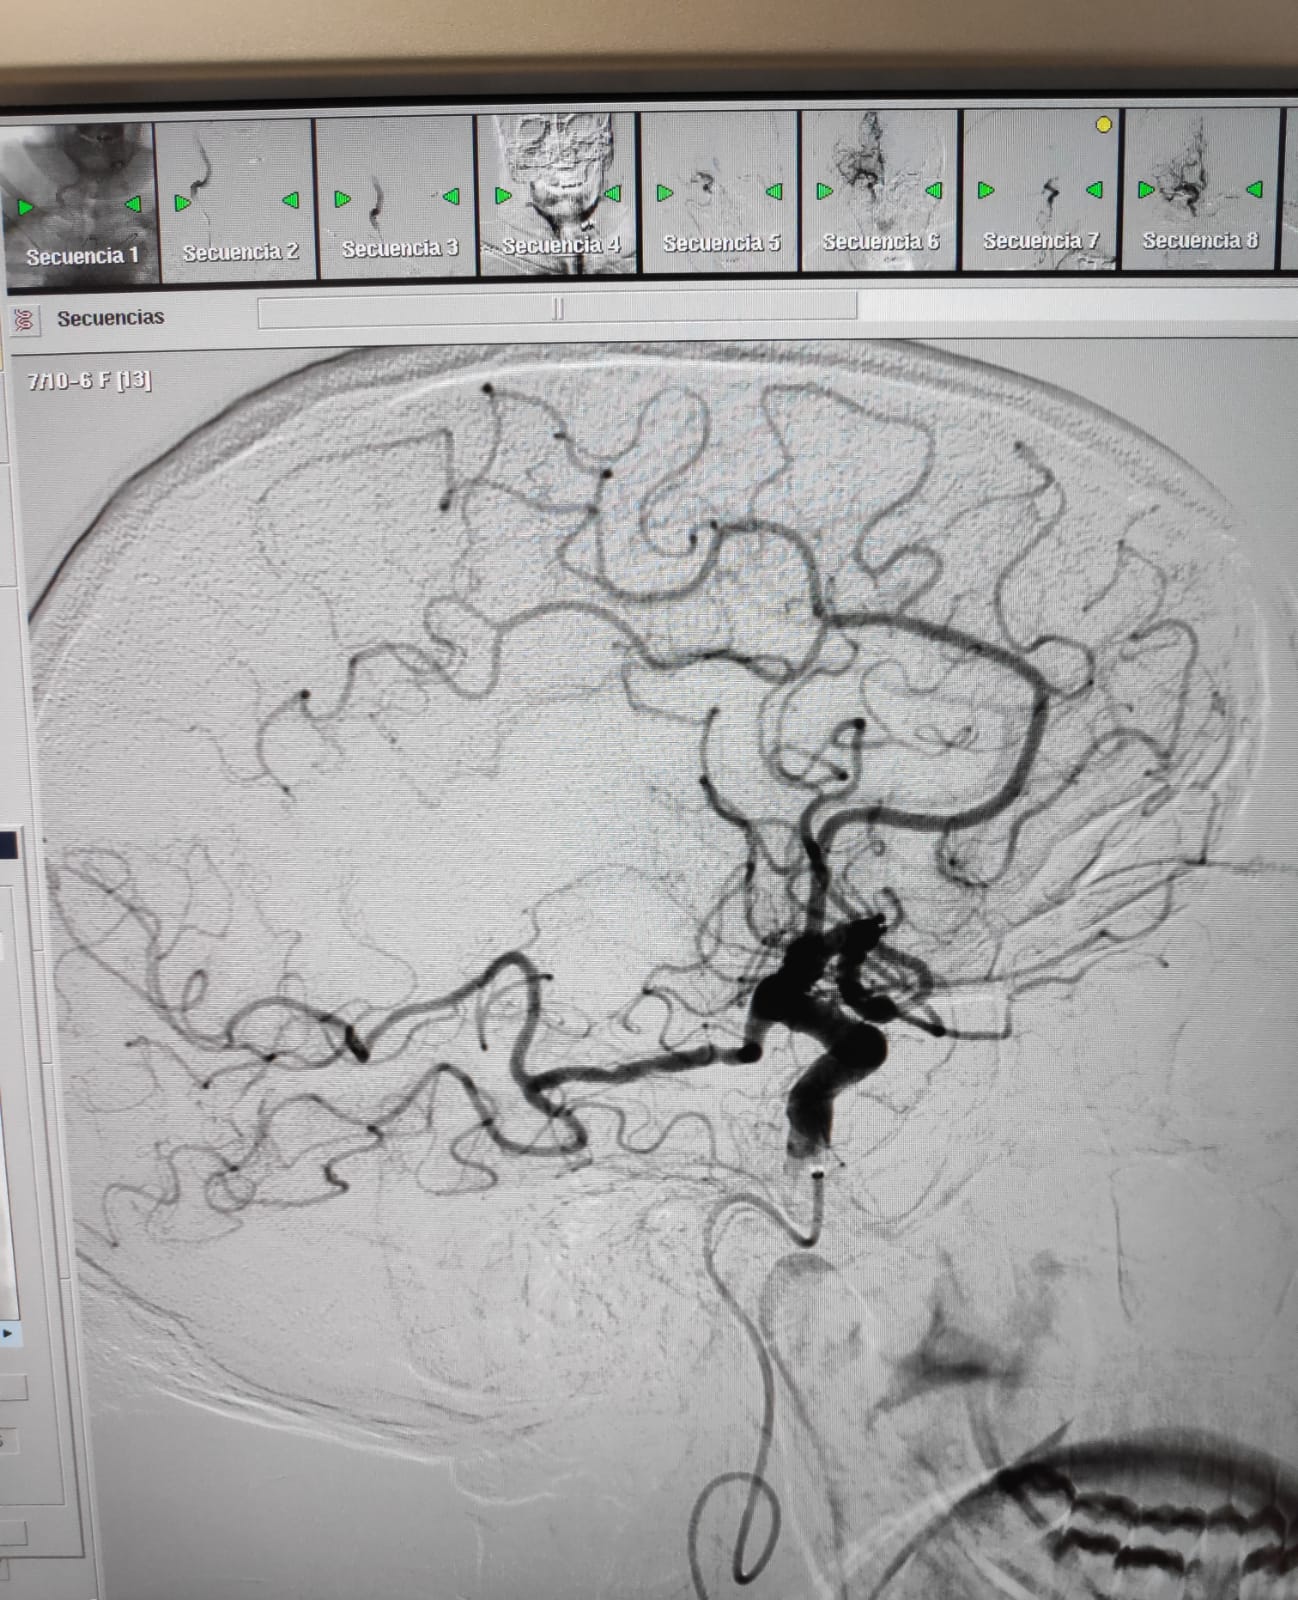

En aquestes dues imatges, podem veure com queda afectada la circulació arterial arran d'un ictis isquèmic i com es recupera després del tractament endovascular.